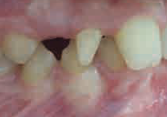

Il existe aussi des anomalies de forme, comme :

- les dentsLes dents sont des organes de la bouche, constitués des tissus les plus minéralisés du corps humain. Chez l’homme deux générations de dents se succèdent : les dents de laits et les dents définitives. Elles permettent la mastication : première étape de la digestion. Elles sont au nombre de 20 pour les dents de lait et 32 pour les dents définitives. (cf aussi dents de lait) en cône

- en grain de riz

- les dentsLes dents sont des organes de la bouche, constitués des tissus les plus minéralisés du corps humain. Chez l’homme deux générations de dents se succèdent : les dents de laits et les dents définitives. Elles permettent la mastication : première étape de la digestion. Elles sont au nombre de 20 pour les dents de lait et 32 pour les dents définitives. (cf aussi dents de lait) fusionnées (deux bourgeons dentaires unis)

- ou encore les géminées (un seul bourgeon partiellement divisé)

Riziforme